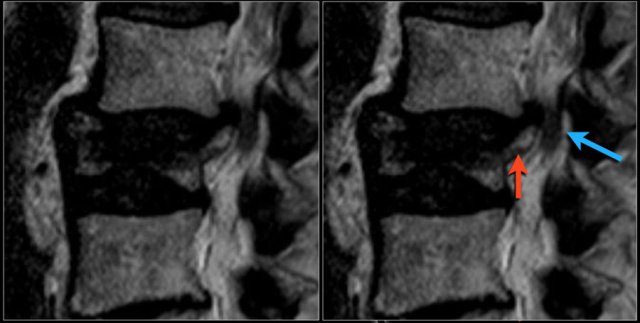

Fractures can cause stenosis of the spinal canal especially when there is displacement of bony structures like in burst fractures and fractures with rotation and translation.

Here a patient with an old burst fracture.

There is retropulsion of the posterosuperior fragment (red arrow) compressing the cauda (blue arrow).